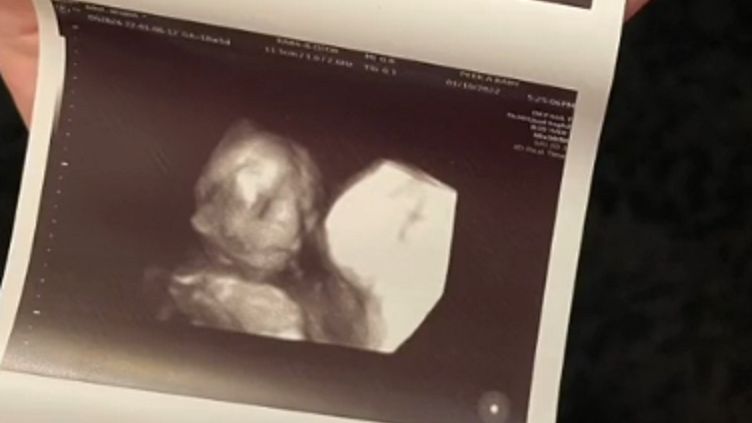

Niedawno przyszła mama wykonała pierwsze badanie USG 3D. Nie spodziewała się jednak, że na pozór niewinne badanie, wprawi ją w przerażenie.

17-tygodniowy płód ułożył się w taki sposób, jakby patrzył się wprost na sondę ultrasonograficzną. Przez to ma złowrogi wyraz twarzy, którego młoda mama kompletnie się nie spodziewała. Jak przyznaje, poczuła się niekomfortowo i początkowo bała się spojrzeć na zdjęcie.

- Moja dziewczynka wygląda strasznie, ale z dnia na dzień robi się słodsza - mówi Ariann.

Przyszła mama postanowiła podzielić się swoją reakcją z użytkownikami TikToka, którzy ją obserwują. W komentarzach przyznali, że również odbierają zdjęcie w ten sam sposób.